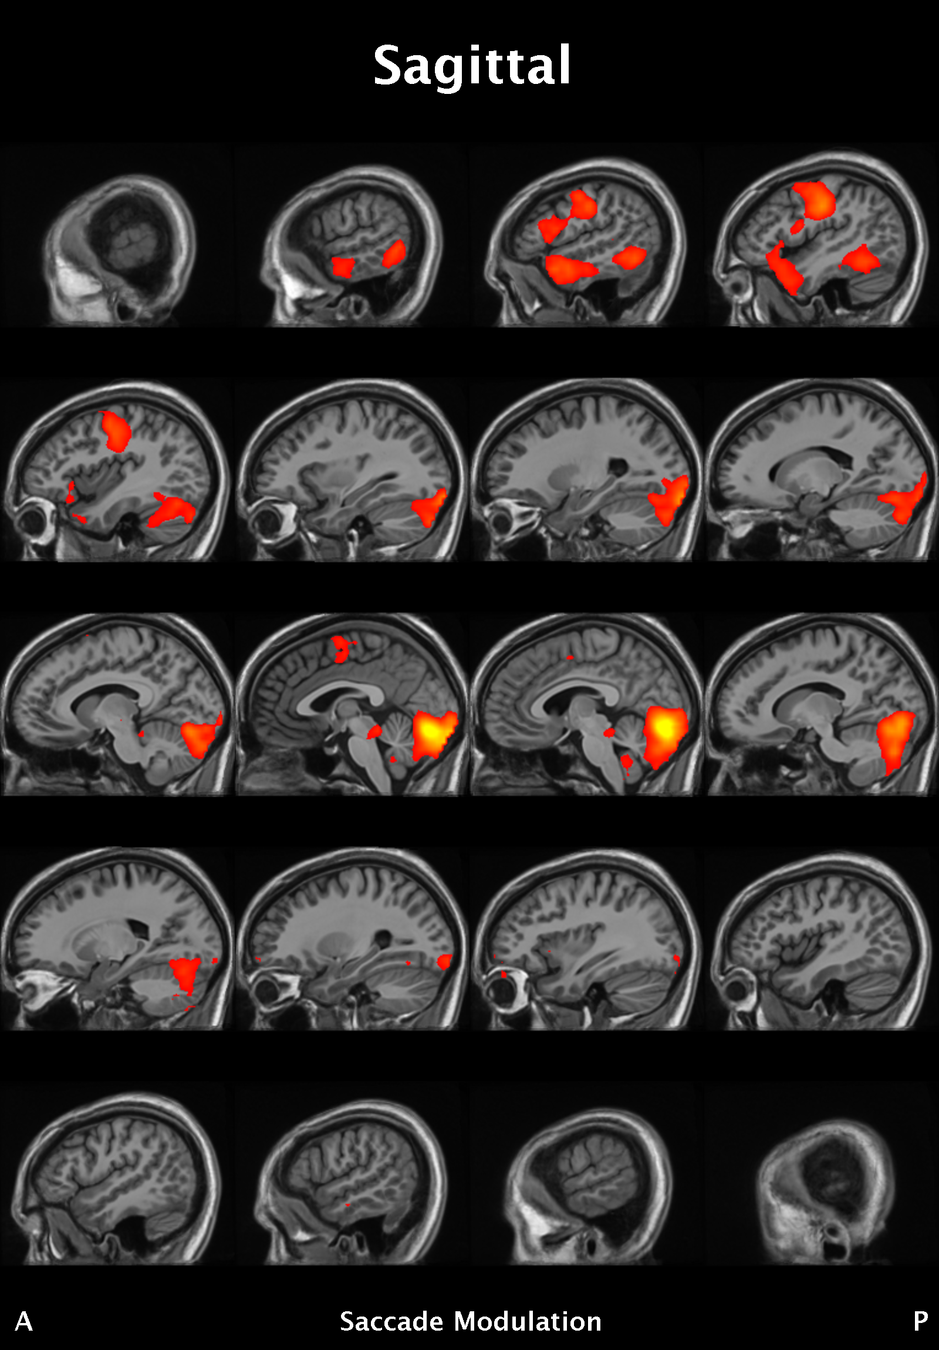

Results

Significant ROIs

Voxels Peak - x Peak - y Peak - z Anatomical location

1923 -1.5 79.5 -9 R/L Lingual Gyrus

495 52.5 -10.5 -18.0 L. Mid. Temporal Gyrus

395 46.5 16.5 33.0 L. Precentral Gyrus

135 1.5 38.5 -12.0 L. Ant. Cerebellum

56 7.5 19.5 -3.0 L. Thalamus

55 -22.5 -94.5 -9.0 R. Inf. Occipital Gyrus

55 52.5 -7.5 15.0 L. Inf. Frontal Gyrus

54 4.5 7.5 60.0 L. Medial Frontal Gyrus

29 -46.5 -7.5 -24.0 R. Temporal Pole